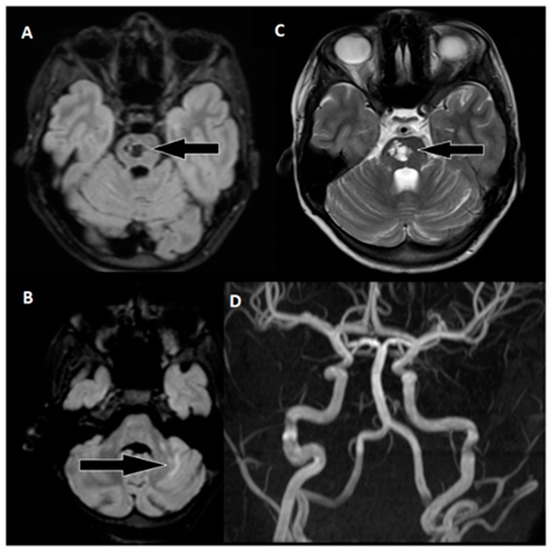

To restore normal blood flow to the affected areas, an aspiration catheter known as “Sofia” (Terumo, Tokyo, Japan) was carefully positioned in the distal V2 segment. Throughout the procedure, multiple left vertebral arteriograms were performed, consistently illustrating blockages in the middle segment of the basilar artery. After six meticulous attempts, a final angiogram conclusively confirmed the complete removal of the obstructions in both the basilar artery and the posterior cerebral arteries, achieving a TICI scale score of 3, indicating full and successful revascularization (Figure 3).

Figure 3. Neurointerventional procedure. (A,B) Initial angiogram from anterior–posterior and lateral views reveals an upper third basilar artery occlusion and no enhancement in both posterior cerebral arteries (TICI scale: 0). (C,D) After the first attempt, angiogram views show improved basilar artery enhancement, but filling defects and absent enhancement persist in both posterior cerebral arteries. (E,F) Post-thrombectomy angiograms demonstrate enhanced perfusion in the basilar artery and both posterior cerebral arteries (TICI scale: 3).